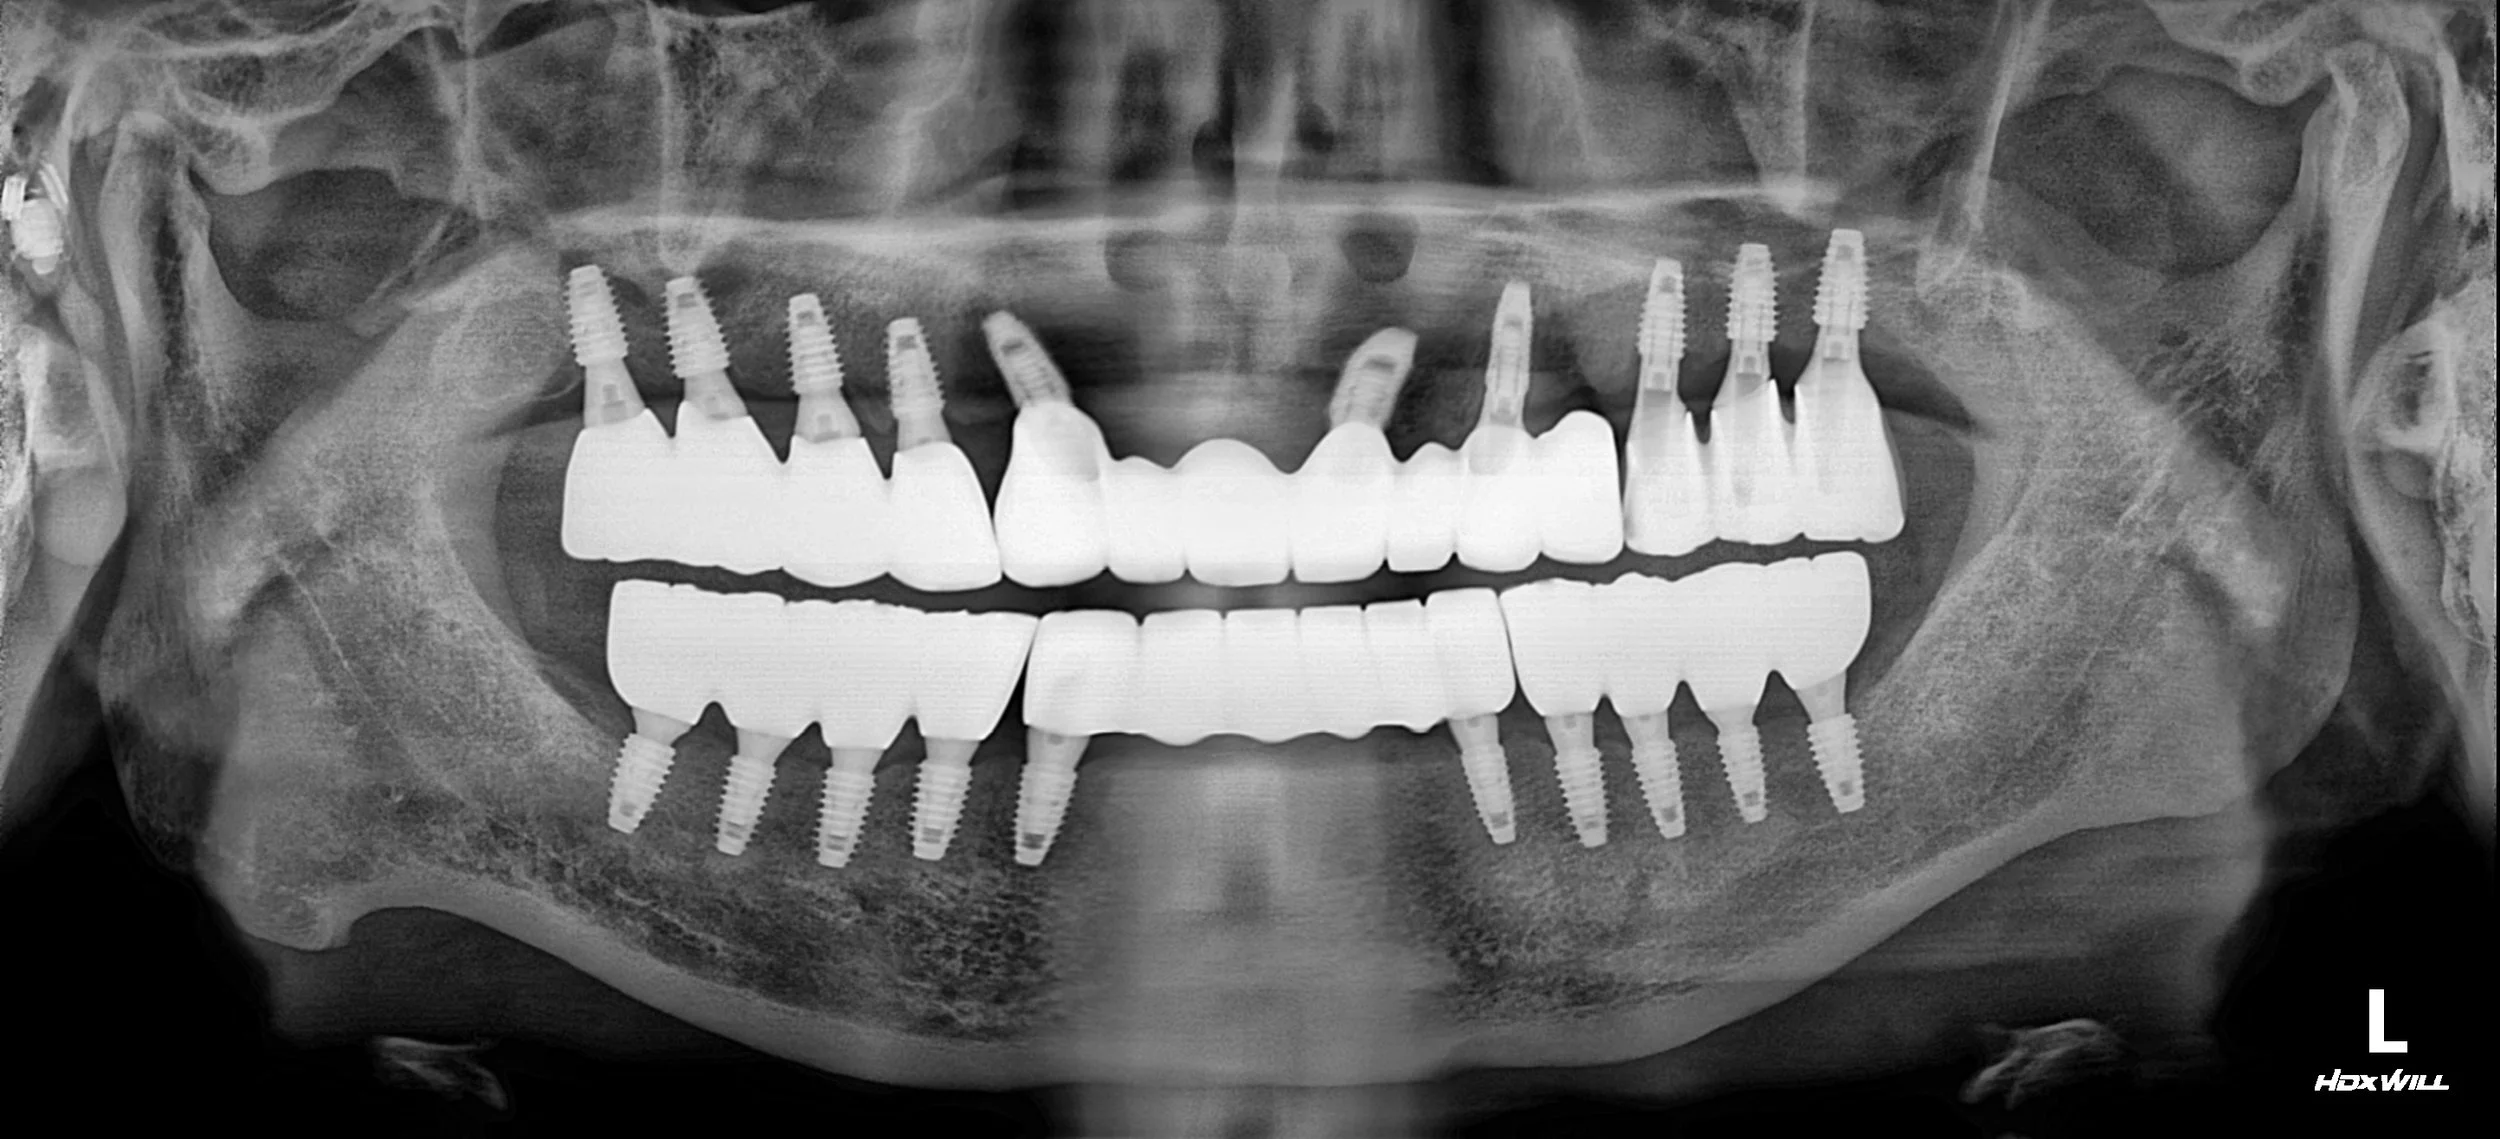

OPG - BEFORE

1. Surgical Phase: hopless teeth and the failing anterior bridge were removed. Multiple dental implants were strategically placed across both arches. In areas of severe bone deficiency, site-specific bone grafting was performed to ensure long-term implant stability and proper prosthetic emergence profiles.